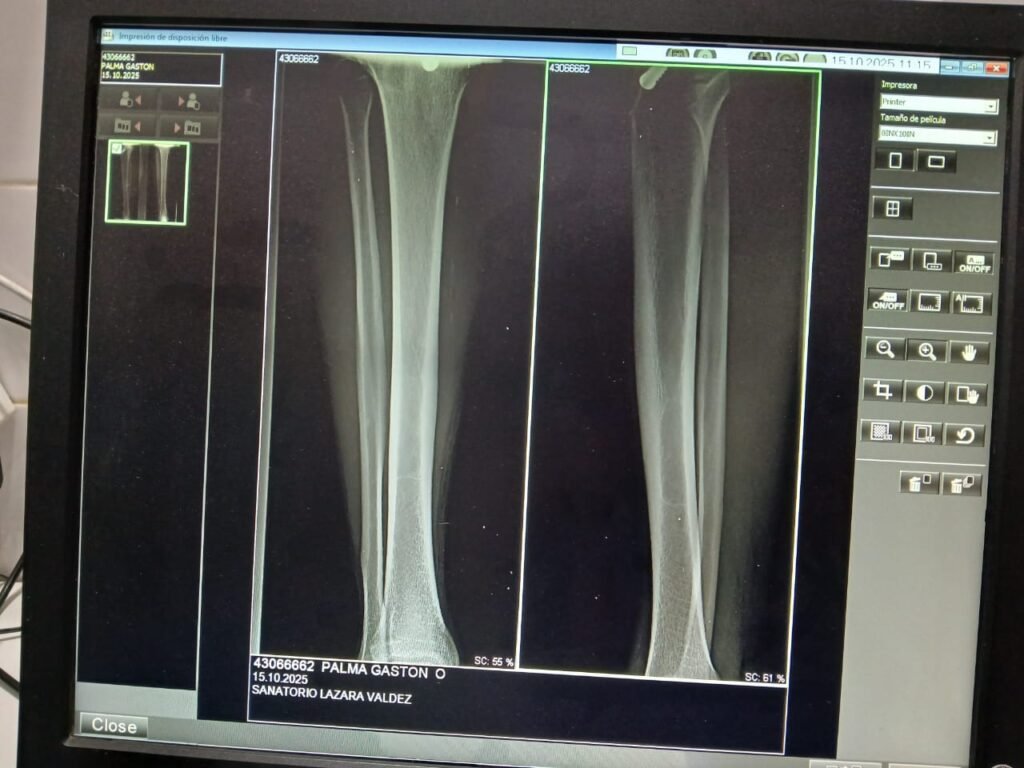

El Cabo Gastón Palma, numerario de la División Infantería de J.J. Castelli, recibió atención médica luego de resultar lesionado durante los graves hechos ocurridos en la tarde del 14 de septiembre en la localidad de Villa Río Bermejito.

Según informó la División de Medicina Legal, el personal policial fue trasladado a su domicilio para monitorear su estado de salud y realizar la curación de la herida sufrida. Se trata de una lesión de aproximadamente 3 centímetros en la cara anterior de la pierna derecha, que fue suturada con tres puntos.

Durante el control médico se constataron signos vitales normales y una evolución favorable de la herida. Además, una radiografía confirmó que no se produjo afectación ósea. El médico particular del cabo, el Dr. Félix Ruiz, indicó el uso de antibióticos y analgésicos, y aseguró que el agente se encuentra en buenas condiciones de salud.